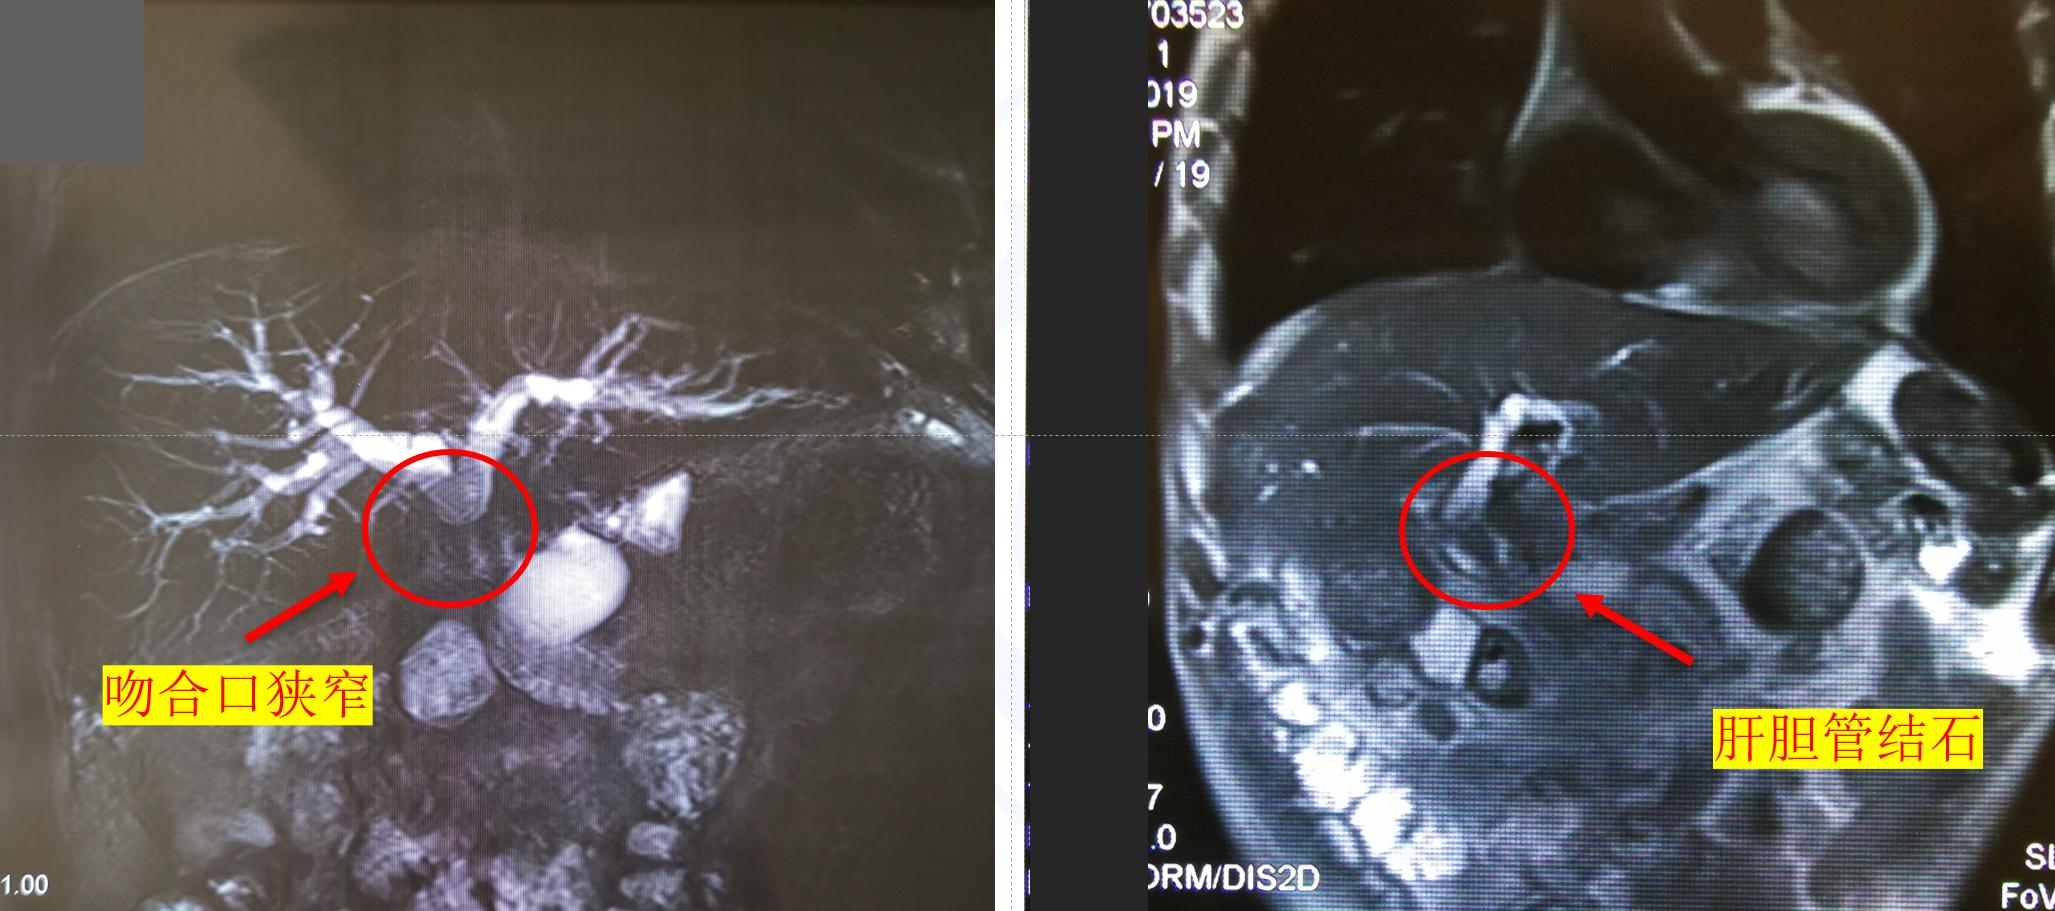

胆管空肠吻合是切除胆管后重建的主要方式,被广泛应用于各种胆道疾病的手术治疗中。尽管该吻合方式可使胆汁顺利进入消化道,但破坏了胆道系统的正常生理结构。胆肠吻合口在愈合过程中受各种因素的影响,会发生瘢痕挛缩,严重者会出现胆肠吻合口狭窄和肝内胆管多发结石。胆肠吻合口狭窄的处理方式较多,既往以再次手术重建为主。反复多次手术不仅难度大,也给患者带来巨大的痛苦。如何以更小创伤改善狭窄值得思考。

胆肠吻合口狭窄可造成胆汁排出障碍,胆汁会淤积在肝内形成黄疸,引发肝内胆管结石、胆道感染等,严重者甚至发展为胆汁性肝硬化。对于已形成胆肠吻合口狭窄的患者,最经典的治疗方法是吻合口拆除重建,但患者需经历数次手术,腹腔粘连严重,手术难度大,且手术重建胆肠吻合口后易再次发生狭窄 。随着微创理念的逐渐推广,利用非开腹手术方式处理胆肠吻合口狭窄的方法日益增多,如PTCS下球囊扩张术、ERCP辅助下支架植入术等。其根本关注点在两方面,即入路选择和扩张手段。

对于入路选择,由于胆肠吻合口狭窄的患者多出现肝内胆管扩张,通常优先选择行PTCS术。一般优先选择扩张的左侧肝内胆管作为穿刺入路,避免胆道镜进出角度过大造成操作困难。目前,狭窄扩张方法有高频电刀切开、球囊扩张或支架等,均能取得满意效果。首次手术一般仅建立入路,除非患者严重感染,否则均将狭窄扩张放至后期经皮胆道镜术中。胆道镜下先针刀切断缩窄的纤维环,然后置入球囊进行扩张。狭窄环较短的患者,宜选择柱状水囊;如狭窄环距离较长,则宜选用扩张力度更大的球状水囊。针刀联合球囊的方式不仅可以将纤维瘢痕组织切断,亦可运用球囊扩张更好地进行狭窄整形,在不同的吻合口狭窄处理上更灵活。多数病例经过2-3次扩张,胆肠吻合口可扩张至0.7cm以上。

值得注意的是,胆肠吻合口狭窄患者常合并较多肝内胆管结石,在结石未有效清除前胆道镜不能直接到达胆肠吻合口,不能及时、有效地对胆肠吻合口狭窄进行扩张治疗。另有部分胆肠吻合口狭窄患者的肝内胆管扩张并不明显,导致穿刺困难无法行PTCS术;或者部分患者虽穿刺成功,但胆道镜无法有效到达狭窄的胆肠吻合口。而ERCP技术的发展,使这部分患者免于再次手术治疗。内镜到达吻合口后,可对吻合口进行球囊扩张,植入胆道内引流管并进行取石操作。对于吻合口炎性或瘢痕狭窄的患者,也可植入金属支架,对狭窄进行缓慢而持续的扩张6-12月,有利于防治吻合口扩张后的再次狭窄。